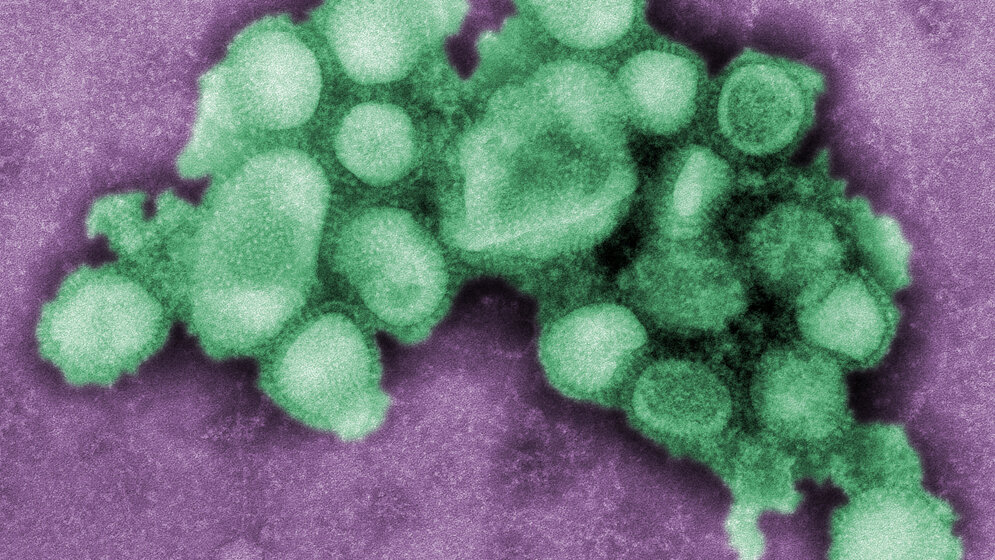

Laut Wellcome Trust werden die COVID-19-Kosten etwa 11 Billionen USD bis Ende 2021 betragen. Das Nicht-vorbereitet-sein kostet deutlich mehr als die Eindämmung von Infektionskrankheiten. Viele Ausbrüche schaffen es noch nicht einmal in die Nachrichtensendungen. Anbei finden Sie die „Top 10“ der vergangenen Jahre. Quelle: WHO/IHM data as of 12 January 2018